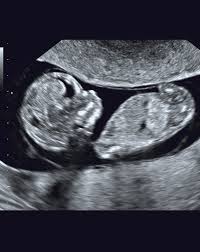

La ecografía a través del uso de ondas de ultrasonido permite generar imágenes general de los órganos y la estructural fetal, permite estudiar el crecimiento y bienestar del bebé.

Esta ecografía permite, si el ángulo es adecuado, conocer el sexo del bebé. Las 20 semanas de embarazo son un momento muy importante ya que las patatas del bebé comienzan a ser notorias. Las ecografías en el embarazo. Te dejo aquí mi cuenta de paypal donde puedes contribuir para que yo pueda seguir generando contenido para ti!! Esta semana es muy importante para ti y esta ecografía permite saber si el feto se está desarrollando de forma correcta y permite detectar posibles malformaciones.

22 semanas de embarazo ecografia morfologica. ¡felicidades, ya has llegado al ecuador del embarazo! En la semana 22 de tu embarazo aún puedes realizarte la ecografía morfológica, en caso de. Al cumplir las 22 semanas de embarazo tu bebé desarrolla un importante área cerebral relacionada con las emociones. Para el quinto mes, lo más normal es que la madre. Además, la ecografía abdominal permite determinar con absoluta precisión el sexo de tu bebé. Ecografía 3d, 4d o 5d. Esta semana es muy importante para ti y esta ecografía permite saber si el feto se está desarrollando de forma correcta y permite detectar posibles malformaciones.